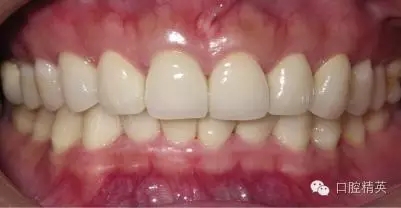

關(guān)于基礎(chǔ)治療。牙周治療和根管治療是美觀修復(fù)的基礎(chǔ)。根據(jù)術(shù)前檢查,常規(guī)先行全口潔治,必要時局部深層次的牙周治療,待牙周情況穩(wěn)定后,再考慮牙體預(yù)備與取模(見圖1、2)。在牙周炎未控制或牙齦紅腫的情況下,是不可能預(yù)備好牙齒,不可能取得清晰的印模,更談不上成功的美觀修復(fù)。

LAVA 全瓷冠強度高,顏色自然,邊緣高度密合,切端可見半透明感,整體效果理想,與修復(fù)前(見圖1)相比取得了醫(yī)患均滿意的效果。